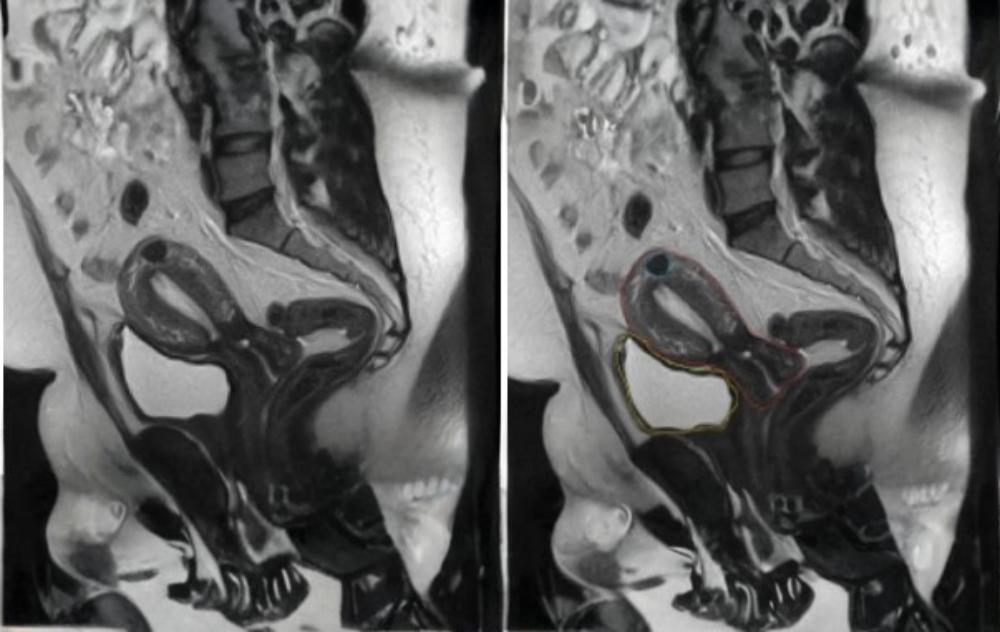

Fibroid Belly Pictures Using MRI

An MRI is one of the most effective ways to visualize fibroids without radiation exposure. Here is what to expect during the 30-minute scan:

To help you navigate these images, the patient’s back is to the right, and their front is to the left.

- The Uterus (Red): The MRI offers a crystal-clear view of the uterine layers compared to a traditional ultrasound.

- The Bladder (Yellow): This sits just in front of the uterus, showing how the two structures interact.

- The Fibroid (Blue): The dark object at the top of the uterus is a small fibroid.

While the fibroid in this example is small, many patients deal with multiple, larger growths that significantly alter the shape of the uterus, as seen in the following scans: